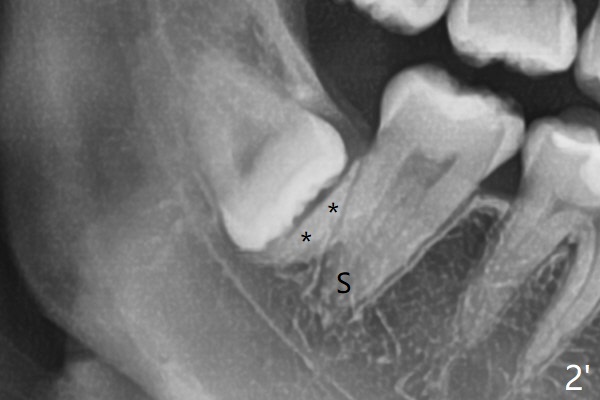

A 31-year-old woman returns with chief complaint of "occasional, mild pain in the lower left 3rd molar" 1 year post extraction of #1 and 16 (Fig.1,2). The lower 2nd molars appears to have a single fused root (Fig.2',2'' S); the radiopaque image mesial to the tooth #32 must be the dense bone (Fig.2' *). In contrast the cortex coronal to the tooth #17 is lacking (Fig.2'' v), as compared to that in Fig.2'. It seems that the bone loss at #17 is associated with mild pericoronitis. The tooth #17 should be extracted with placement of Bond Apatite to repair #18 distal defect. In fact sticky bone and collagen plug are placed instead (Fig.3), covered by 2 pieces of PRF.